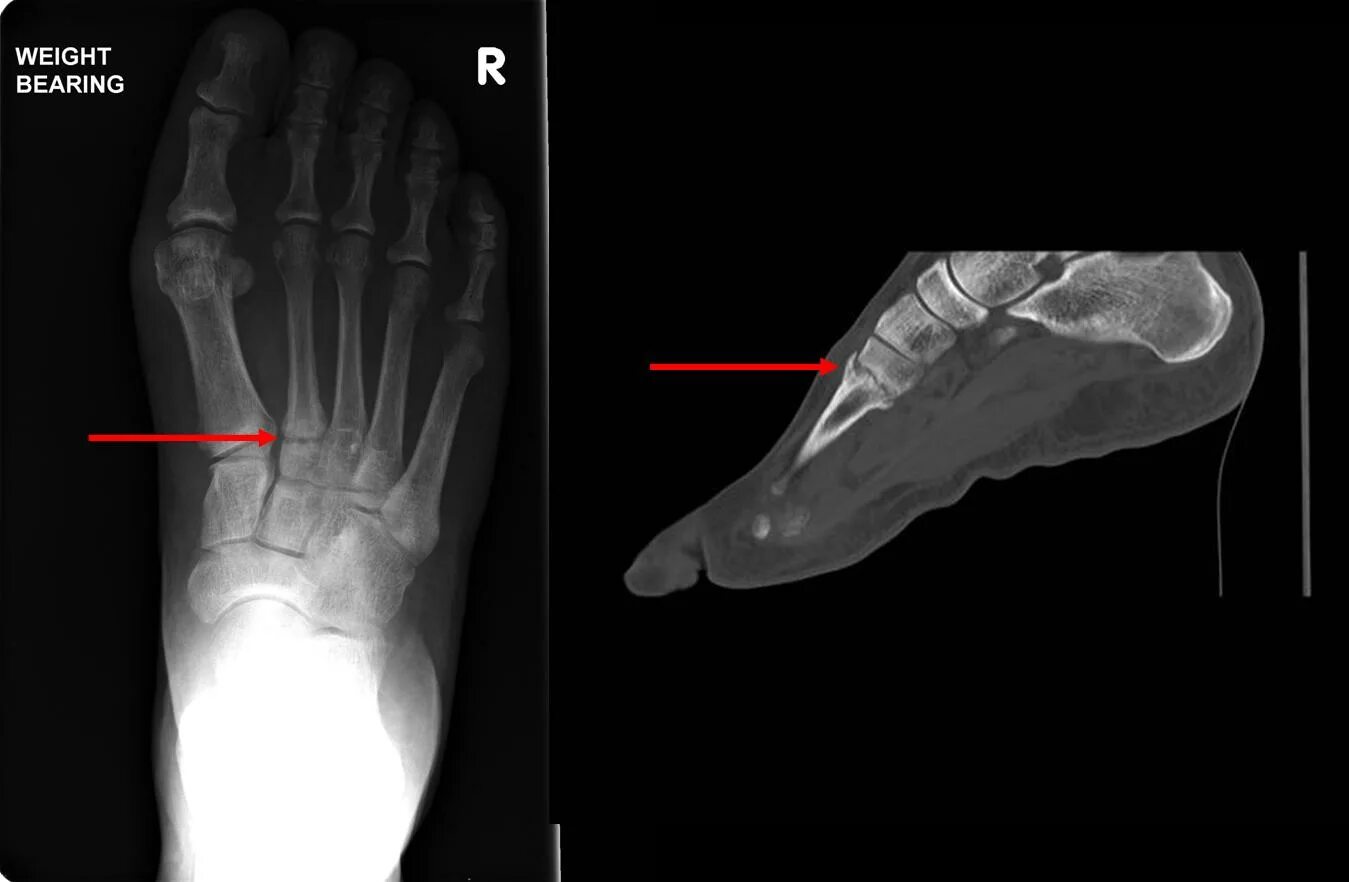

Как определить перелом стопы